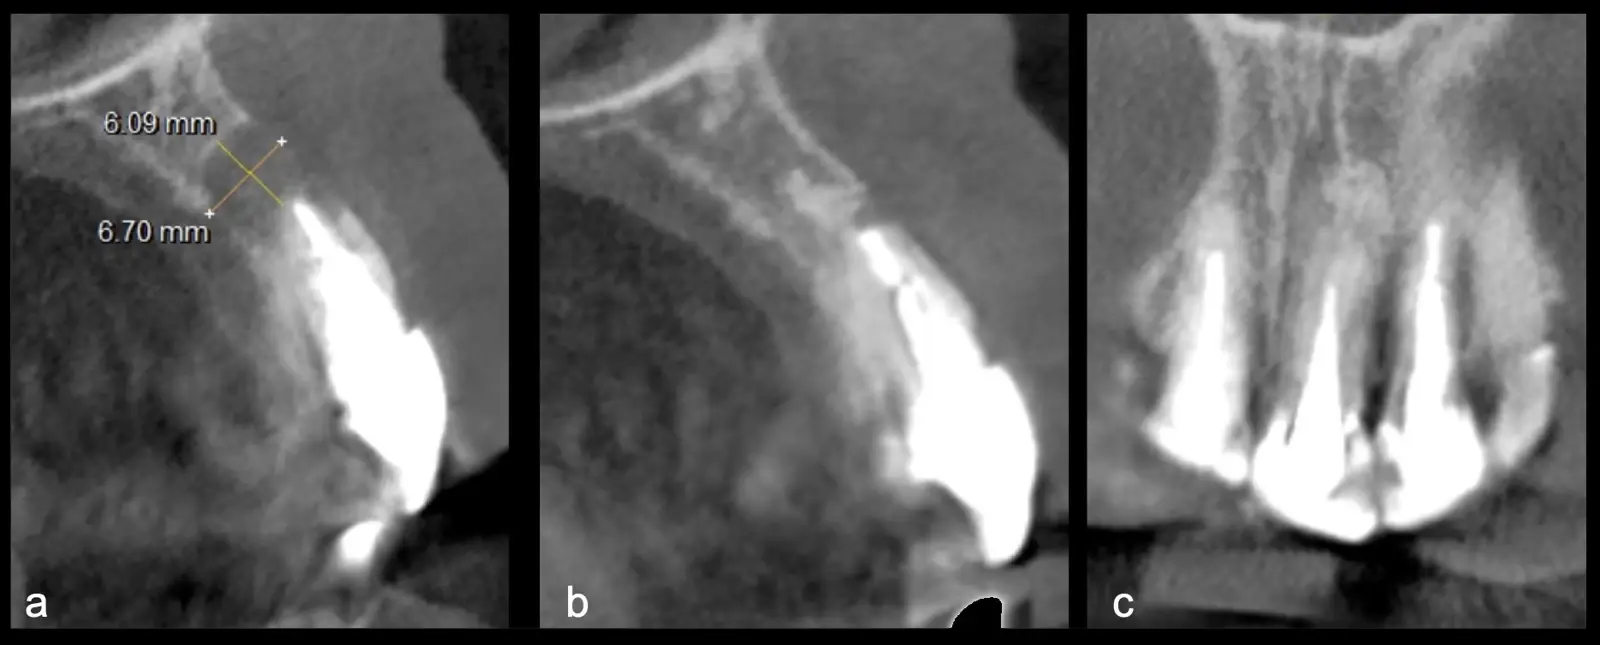

La microcirugía endodóntica apical busca conservar la mayor cantidad de longitud de raíz y de hueso circundante sano para no afectar la estabilidad de la pieza.11 Por ello, es ideal el uso de microscopios, elementos de magnificación, instrumental específico (insertos de ultrasonido endodónticos) y materiales de sellado eficientes para el tratamiento retrogrado. Su éxito es alto y evidencia una cicatrización ósea completa en el 74% de los casos al año de tratamiento.12 Cabe destacar que este logro está asociado también, a predictores propios de cada paciente, como la edad, tipo de pieza, profundidad de sondaje y extensión de la lesión.1 El uso complementario de la tomografía computarizada es resaltante como el instrumento imagenológico de elección para la etapa de planificación microquirúrgica,13 ya sea para una ejecución a mano alzada o con guías prefabricadas.14,15

El procedimiento se inicia colocando anestesia y elevando un colgajo mucoperióstico a espesor completo3 (incisión semilunar o intrasurcular con/sin protección papilar) y exponiendo la zona. En seguida se realiza la enucleación de la lesión, eliminando16 o creando una ventana17 en la lámina cortical que contiene el área del ápice; este retiro óseo se realiza con los insertos de forma aplanada dentada o inserto con cobertura diamantada plano o redondo, recordando ser lo más conservador posible (Figura 5).

Una vez limpia la zona apical, se corrobora la integridad de la raíz y se evalúa el grado de extensión de la lesión. Si el defecto óseo es pequeño, se procede a realizar la preparación del conducto y obturación retrógrada de ser el caso. Si el defecto óseo es de gran tamaño e inaccesible a los insertos, se procede a realizar un corte de por lo menos 3 mm de ápice radicular conteniendo los posibles conductos aún infectados11 empleando habitualmente insertos de borde aserrado con/sin marcas de medición para un trabajo seguro7 (Figura 7).